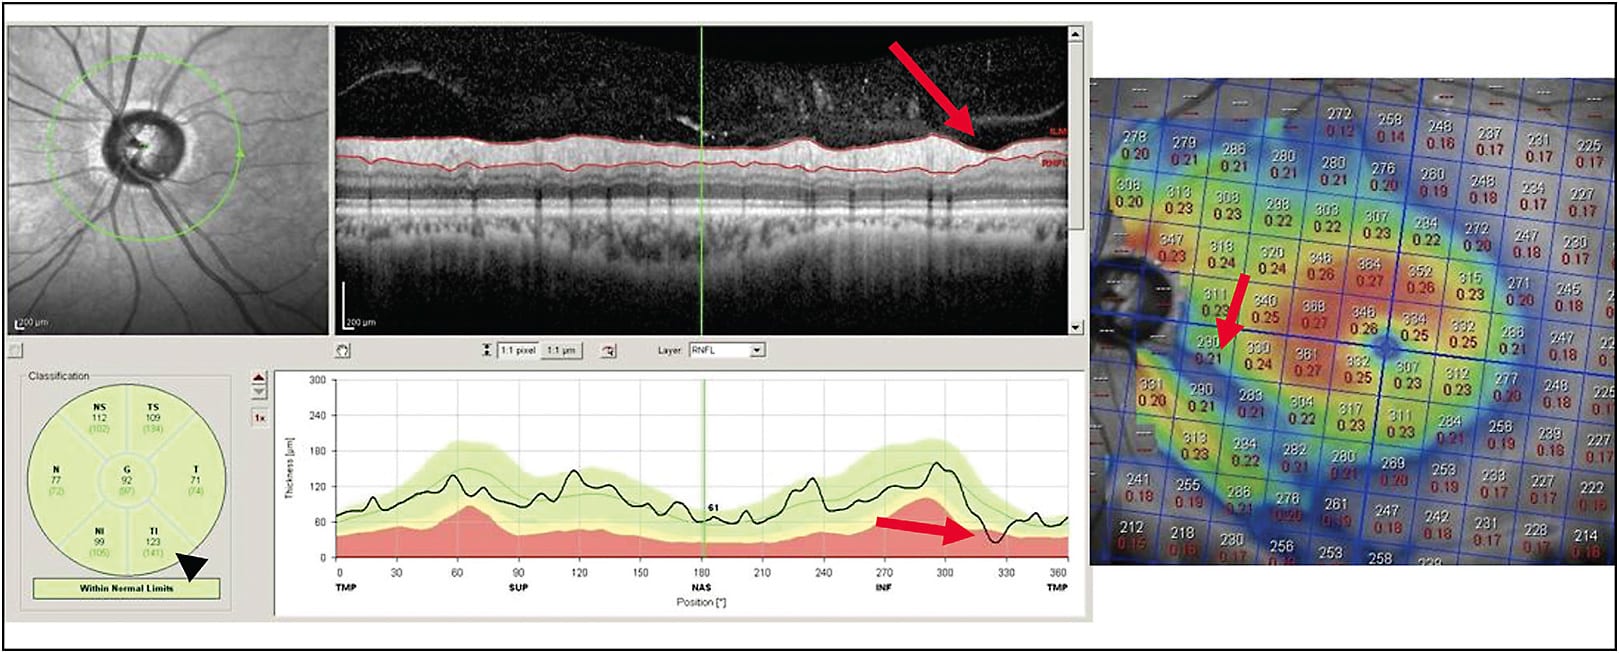

Macular thickness scans are an invaluable tool for the glaucoma provider and provide a significant amount of information in addition to the RNFL thickness. OCT software is typically able to compare total macular thickness scans and also the specific layers of the retina containing the ganglion cell complex (GCC), made up of the nerve fiber layer, ganglion cell layer, and inner plexiform layer. Analysis of the GCC alone may eliminate some artifacts related to abnormal anatomy of the outer retinal layers as might be encountered in patients with macular edema or diabetic retinopathy. Using both RNFL and macular thickness scans (either GCC or full retinal thickness) can increase the sensitivity and specificity of OCT for glaucoma. An example would be using both scans together to assist in recognizing so-called green disease. This occurs when the average sectoral thickness on an RNFL report is normal, but in fact a small focal loss has occurred. It is critical to carefully examine the circular scan for focal “pinching” of the RNFL, which indicates focal loss (Figure 1). Concurrent macular scans are more likely to highlight these focal losses by demonstrating an arcuate loss of macular thickness corresponding to the loss of the same anatomic structure (ie, the ganglion cell with its axon). Similarly, if RNFL analysis indicates possible loss of tissue but there are no concurrent macular changes, it may represent artifact or intertest variability rather than true progression.